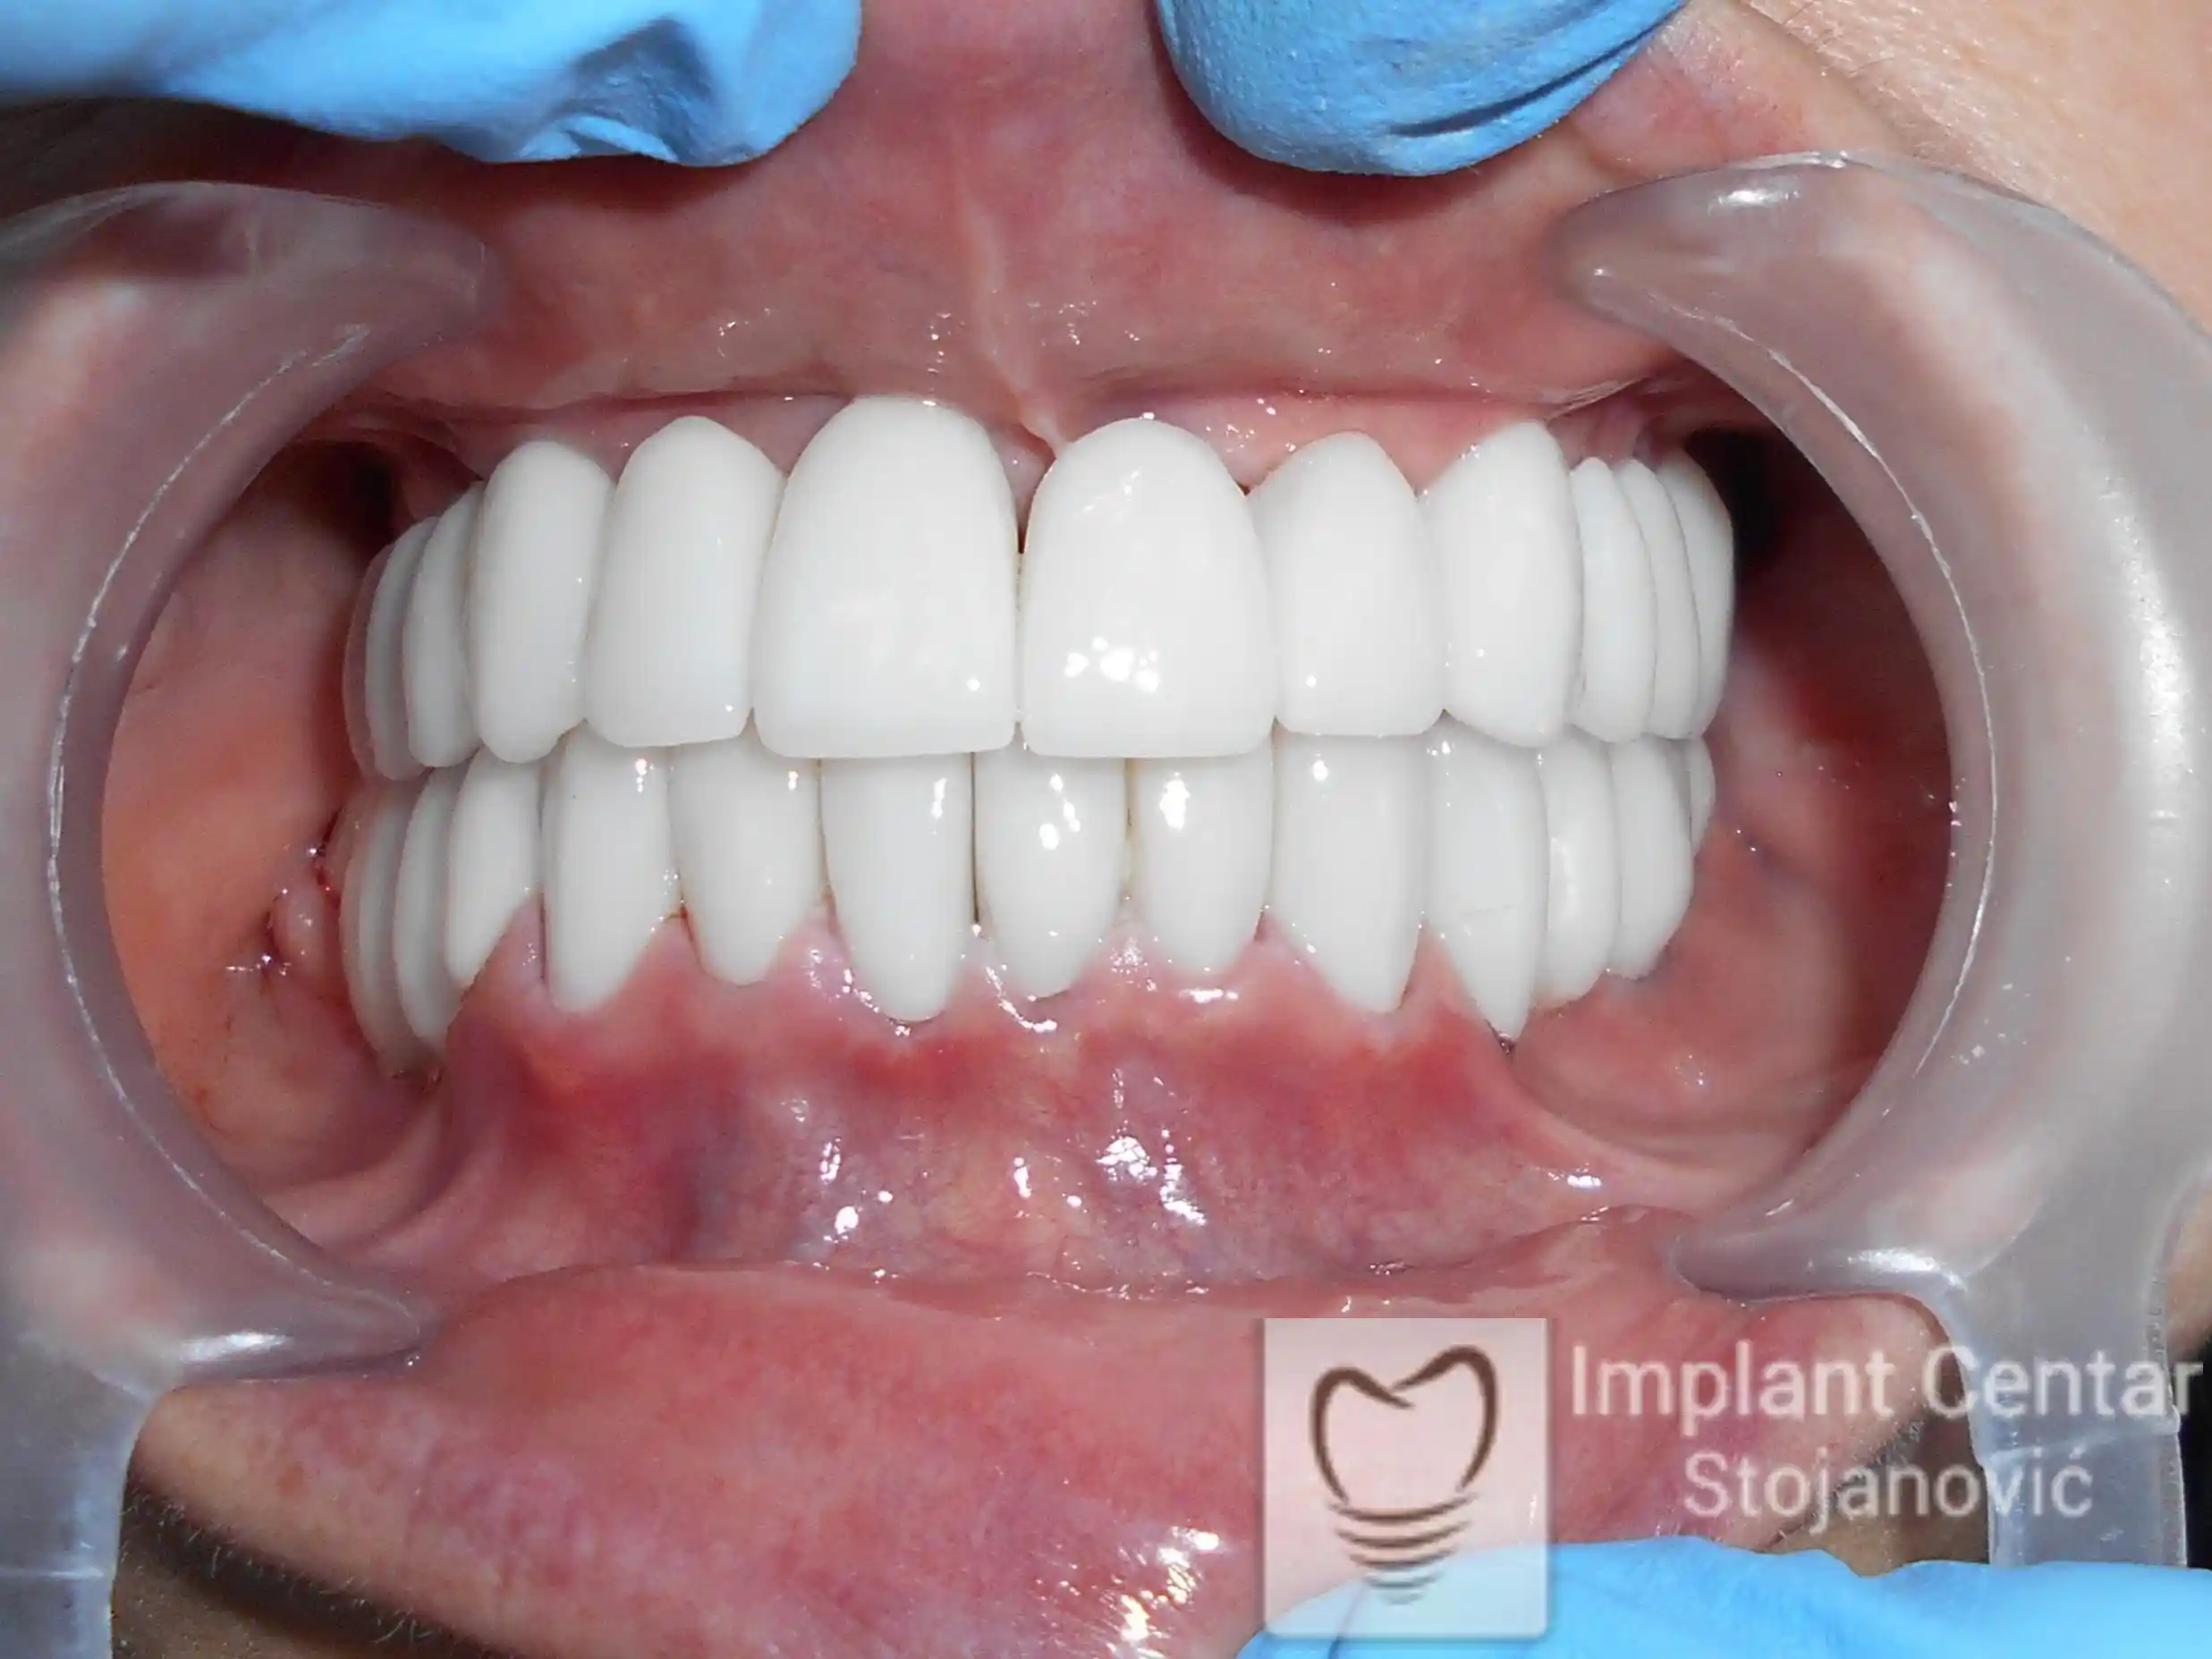

Tokom perioda oseointegracije, pacijent je bio zbrinut fiksnim privremenim krunicama, čime je već pet dana nakon intervencije obezbeđena potpuna funkcionalna i estetska rehabilitacija. Nakon završetka perioda integracije implantata, izrađeni su definitivni cirkonijum-keramički mostovi na implantatima.

Pacijent je izuzetno zadovoljan postignutim rezultatom, navodeći da po prvi put jasno oseća svoje nepce tokom žvakanja, kao i da se smeje sa punim samopouzdanjem.